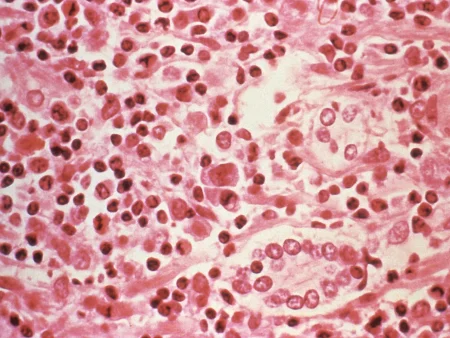

سرطان الكبد المتقدم هو حالة ينتشر فيها السرطان إلى الكبد والأعضاء الأخرى. تشمل الأعراض الشائعة فقدان الوزن غير المبرر، وفقدان الشهية، والإرهاق الشديد، واليرقان، وتورم البطن بسبب تراكم السوائل. في هذه المرحلة، غالبًا ما يتم العلاج باستخدام الأدوية الموجهة، والعلاج المناعي، أو العلاج الكيميائي الموضعي، مع التركيز بشكل أساسي على تحسين نوعية حياة المريض.

ومع ذلك، يؤكد خبراء الأورام على أهمية الكشف المبكر عن أورام الكبد، حيث أن العلاج يكون أكثر فعالية في المراحل المبكرة من المرض. الفحوصات الدورية والتوعية بالعوامل التي تزيد من خطر الإصابة بالمرض، مثل التهاب الكبد الفيروسي وتليف الكبد، يمكن أن تساعد في التشخيص المبكر الذي ينقذ الأرواح. تعتبر أيضاً المتابعة الدورية للمرضى المعرضين للخطر، مثل المصابين بأمراض الكبد المزمنة، جزءاً أساسياً من استراتيجية الكشف المبكر.